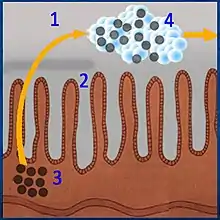

Reabsorption of metabolites and toxic substances in the intestine (Chart) |

PMSPH eliminates reverse absorption of metabolites and toxic substances in the intestine |

Legend

|

Highly viscous PMSPH particles cover mucosal areas and protect them from the damaging effects of bacterial toxins and various active chemical compounds (e.g., deconjugated bile salts that damage the mucosa of the gastrointestinal tract).